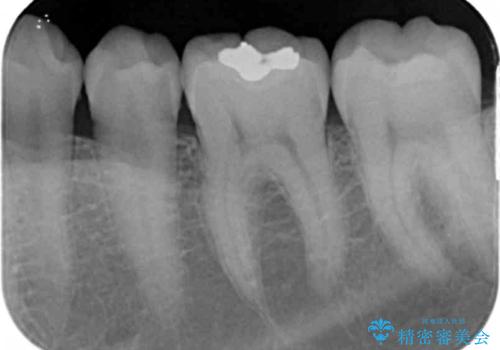

老朽化した銀歯の下には虫歯が大きくなっていることもあるので長期間経過した修復物はX線撮影を行うなどのチェックが重要です。